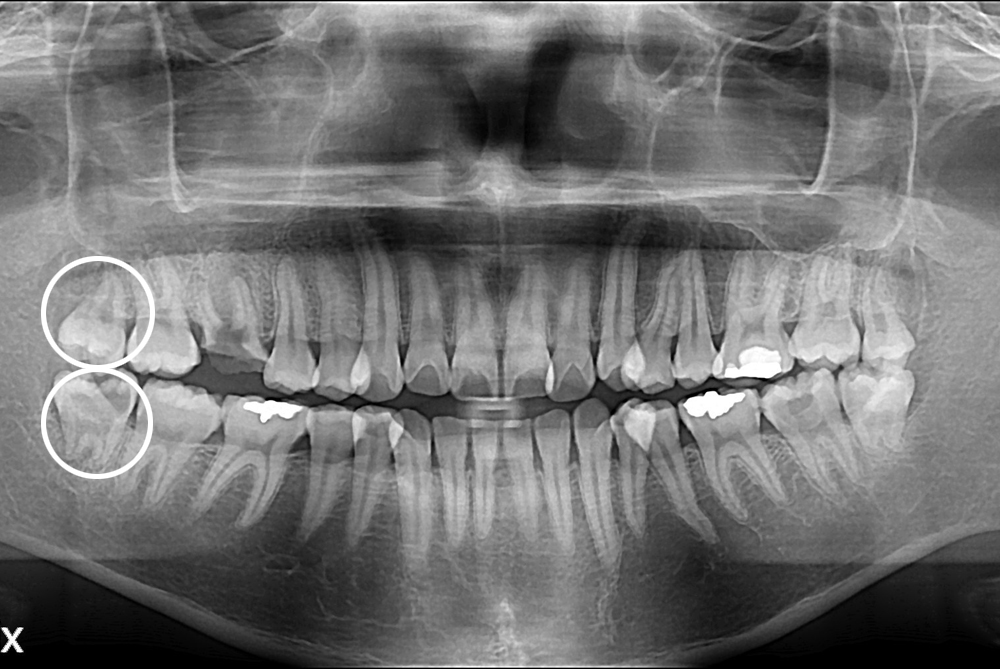

[사랑니] 난발치 사랑니 발치

치료전 : 2017-10-04